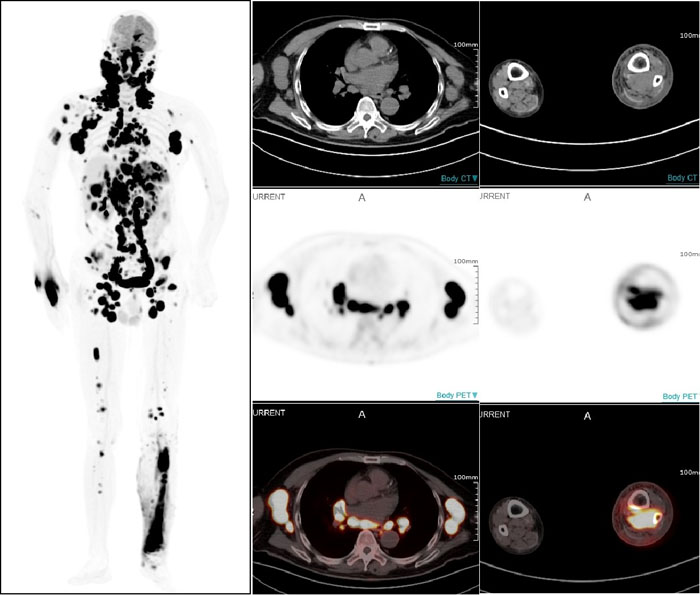

PET/CT显示:全身多部位淋巴结和多个结外器官及不易发现的左小腿后方肌肉组织淋巴瘤受累病灶

一名67岁男性患者因近期无明显诱因出现左颈部淋巴结肿大而就医,淋巴结切检病理诊断为非霍奇金弥漫大B细胞淋巴瘤。借助全景动态Total-body PET/CT扫描,不仅确认了此前的诊断,还发现肿瘤已广泛累及全身多处淋巴结及乳腺、胸膜、肝脏、脾脏、胃等多个结外器官。更令人称奇的是,连平时难以察觉的右小腿深部肌肉组织病变也被准确捕捉。这一全面而精确的影像信息,有效提升了治疗的针对性,为医生制定个性化治疗方案奠定了坚实基础。

设备全身动态采集的性能,清晰展现出药物在体内的流动、扩散及被组织器官摄取并代谢的全过程,帮助医务人员观察药代动力学改变,可以预见,将为肿瘤诊疗、新药研究、细胞追踪等领域带来更多革命性突破‌。